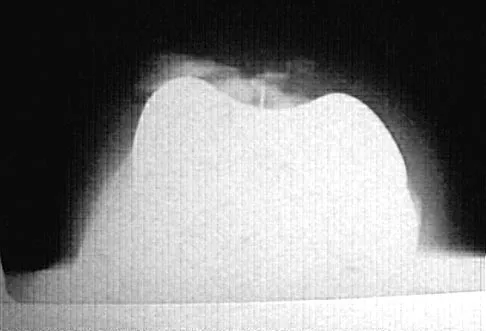

Figure 49 shows the radiograph of a 3-year-old child with progressive bowlegs. Laboratory studies show a calcium level of 9.5 mg/dL (normal 9.0 to 11.0 mg/dL), a phosphorus level of 4.2 mg/dL (normal 3 to 5.7 mg/dL), and an alkaline phosphatase level of 305 IU/L (normal 104 to 345 IU/L). What is the most likely diagnosis?

Explanation